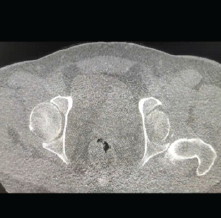

Extraarticular Interfragmentary Fixation of an Irreducible Pipkin Type 1 Fracture Dislocation of the Hip – A Case Report

Dinesh Kale , Sahil Kale , Sanjay Pratheep , Ajit Modak , Ravindra Bharamgunde , Sachin Kale

………………………………p.194-198